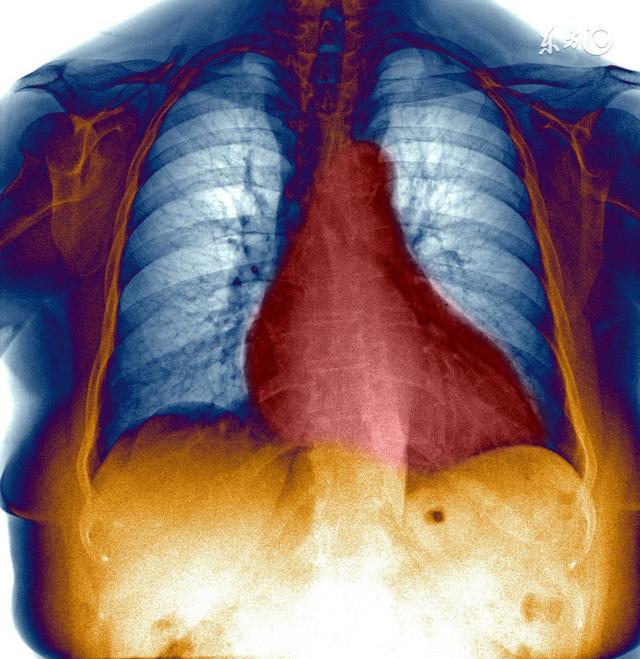

肥大型心筋症は恐ろしい病気で、これは宿命的、つまり遺伝する。臨床では本当にまれな病気です。

肥大型心筋症はとても怖い病気である。 なぜ怖いかというと、心筋が肥大するということは、心臓の部屋がとても小さくなるということだからである。 心臓の部屋が小さいと、心臓が保持できる血液量が少なくなり、排出できる血液量も少なくなる。そうなると、全身の臓器が血液の供給を必要とするわけだが、この血液量で足りるわけがない。そのため、身体は心臓に血液の排出を早めるよう指令を送り、心臓の拍動を速め、心筋を強く収縮させて血液を絞り出し、排出させる。

筋肉が長時間使われるとどうなるか、非常に単純な試みがある。心臓の心筋がより多くの仕事をするのと同じように、筋肉は厚くなり、心筋は厚くなることで代償し、心臓の部屋をさらに狭める。